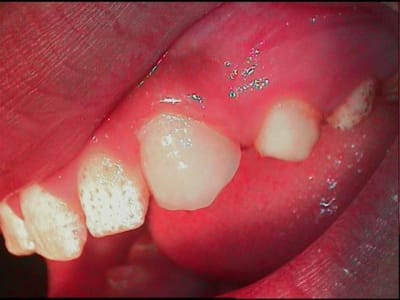

j'ai fait il y a 10jours un test sur 24, grossier! mais pour voir la tolerance

Test prealable sur 24 vv6qwp - Eugenol